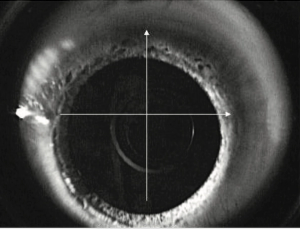

Procedure can improve best-corrected visual acuity, enhancing quality of life for patients.